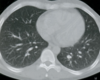

TC ventana pulmonar

Se ven mejor la vía aérea, vasos pulmonares y cisuras, pero todas las estructuras mediastínicas aparecen de un tono gris demasiado similar.